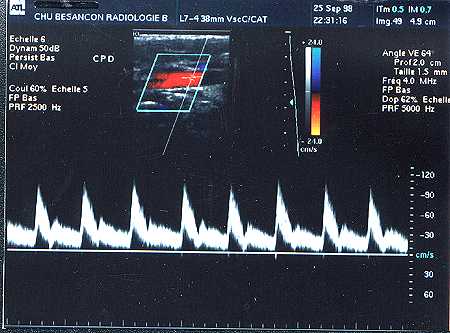

Semnal doppler arteriel normal la nivelul unui membru inferior.

1. Partea initiala a semnalului (ascendenta): rapida

2. Ansamblul semnalului sistolic: scurt

3. corespunde unui semnal de reflux putin amplu si scurt

3'. Si, uneori unui

semnal de 'rebond'.

4. Un timp mort sau non-pulsatil care il separa de sistola

urmatoare